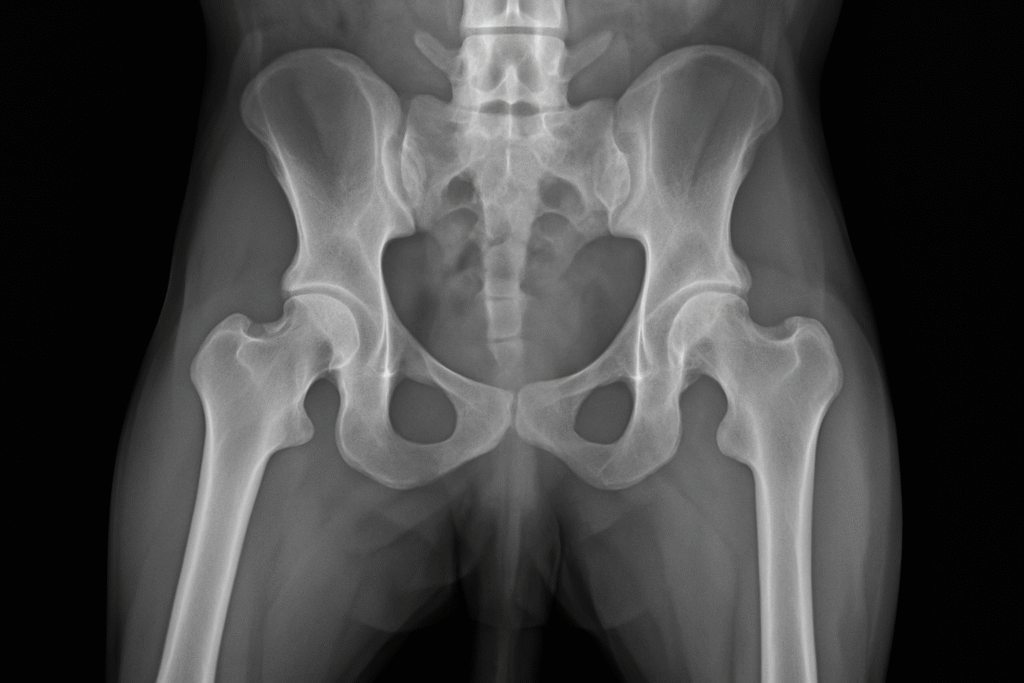

El diagnóstico de la displasia de cadera generalmente se realiza a través de un examen físico y radiografías. Durante el examen físico, el veterinario evaluará la movilidad del perro y buscará signos de dolor o inflamación en las caderas.

Las radiografías son esenciales para confirmar el diagnóstico y evaluar el grado de displasia. Las radiografías permiten al veterinario ver la alineación de la cadera y determinar si el desgaste es suficiente como para requerir tratamiento.